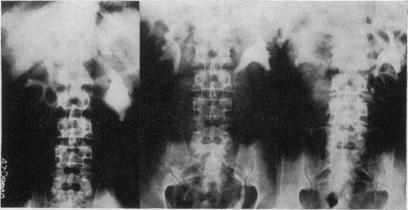

Colocystoplasty for bladder carcinoma after radical total cystectomy.

Ann R Coll Surg Engl. 1970 Jun;46(6):320-37.